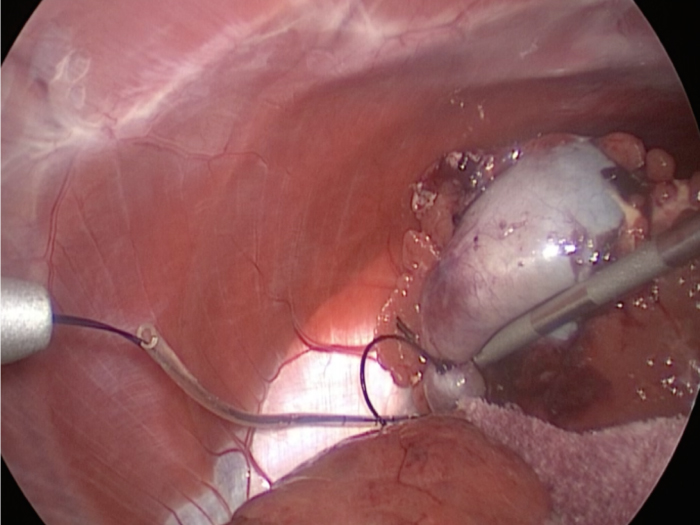

胆嚢の周囲の脂肪や膵臓、十二指腸が激しく癒着し剥離が困難な状態でした。 胆嚢は全く確認することができませんでした。

少しずつ癒着を剥がして胆嚢が確認できるようになってきました。

こんなに癒着していることはあまりないので過去に膵炎や胆嚢炎を起こし苦しい時期があったことが推測されました。

それにしてもなかなか胆嚢はでてきませんでした。

摘出した胆嚢はカチカチで中にはゼリー状の硬い物質が詰まっていました。

手術は丁寧に剥離していったため時間がかかってしまいました。

症状がなかったので、こんなに大変な状態になっているとは。